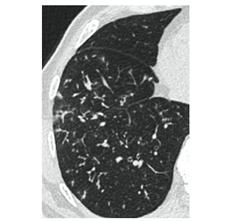

2. Наличие клинических проявлений, указанных в п. 1, в сочетании с характерными изменениями в легких по данным компьютерной томографии (КТ) (см. Приложение 1 настоящих рекомендаций) вне зависимости от результатов однократного лабораторного исследования на наличие РНК SARS-CoV-2 и эпидемиологического анамнеза.

- Изменения при КТ (рентгенографии), типичные для вирусного поражения (объем поражения минимальный или средний; КТ 1-2)

- Изменения в легких при КТ (рентгенографии), типичные для вирусного поражения (объем поражения значительный или субтотальный; КТ 3-4)

- Изменения в легких при КТ (рентгенографии), типичные для вирусного поражения критической степени (объем поражения значительный или субтотальный; КТ 4) или картина ОРДС.

КТ имеет высокую чувствительность в выявлении изменений в легких, характерных для COVID-19. Применение КТ целесообразно для первичной оценки состояния ОГК у пациентов с тяжелыми прогрессирующими формами заболевания, а также для дифференциальной диагностики выявленных изменений и оценки динамики процесса. КТ позволяет выявить характерные изменения в легких у пациентов с COVID-19 еще до появления положительных лабораторных тестов на инфекцию с помощью МАНК. В то же время, КТ выявляет изменения легких у значительного числа пациентов с бессимптомной и легкой формами заболевания, которым не требуется госпитализация. Результаты КТ в этих случаях не влияют на тактику лечения и прогноз заболевания при наличии лабораторного подтверждения COVID-19. Поэтому массовое применение КТ для скрининга асимптомных и легких форм болезни не рекомендуется.